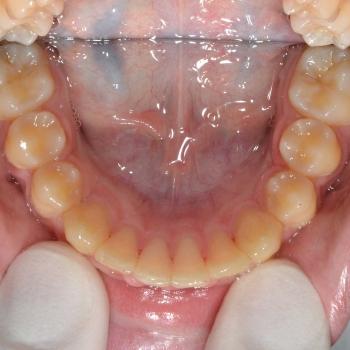

A kezelést Quadhelix fogszabályozóval kezdtük el a felső fogív tágítása érdekében. Ezután került felragasztásra az alsó és felső fogívre a Balázs és szülei által kiválasztott fém önligírozó fogszabályozó. Ezen túlmenően Bite turbo harapásemelő segített a mélyharapás, intermaxillaris gumihúzás pedig az Angle II. osztályú harapási eltérés korrigálásában. A fogak méretaránytalansága miatt a kezelés végén a kismetszőket tömőanyaggal építettük fel, hogy a tökéletes harapáshoz résmentes fogazat társuljon. A fogak felépítéséhez az adott fogakat nem kell megfúrni, a tömőanyag kizárólag ragasztásos módszerrel rögzül, így nem károsodik a fogzománc.

A kezelés teljes időtartama: 2 év